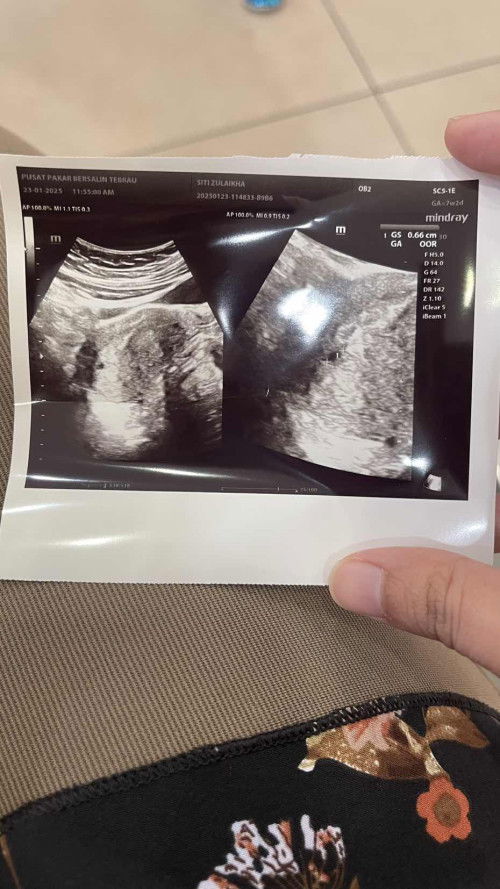

Kantung kecil 7 weeks pregnancy

Hi mommies, harini pergi scan 7 weeks, tapi kantung baru 4-5 minggu. Machine pon tak dapat kira berapa weeks sebab kecik sgt. Doc suruh repeat lagi 2 minggu. Ada sesiapa pernah alami tak? Baby membesar atau tak ye? Saya tengok kantung saya pon macam tak bulat cantik je hmm tapi dr tak cakap apa2 pulak pasal bulatan kantung..saya risau dah dua kali miscarriage hmm#mohonbantujawabbunda #bantujawab #Needadvice #sharing